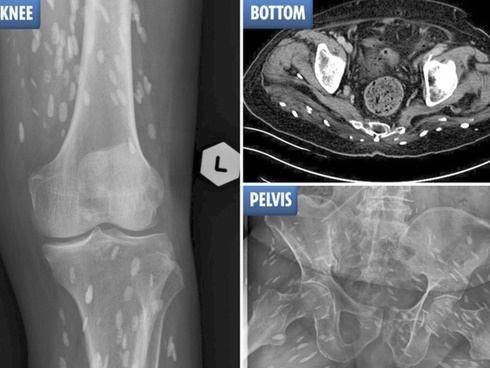

Bác sĩ Vương Giang Vinh tại khoa Truyền nhiễm là người đã thực hiện kiểm tra cho ông Châu và chẩn đoán ông mắc bệnh taenaisis (bệnh sán dây). Bác sĩ Wang cũng phát hiện thấy hơn 700 con sán dây trên khắp cơ thể bệnh nhân.

Chia sẻ trên trang Pear, bác sĩ Vương nói rằng: "Có nhiều sự tổn thương trong não của bệnh nhân. Sán dây cũng có ở trong phổi và lấp đầy các cơ bên trong khoang ngực của ông ấy và gây tổn hại đến các cơ quan".

Bác sĩ Vương nói rằng sán dây đã gây tổn thương đến các cơ quan trong cơ thể bệnh nhân.